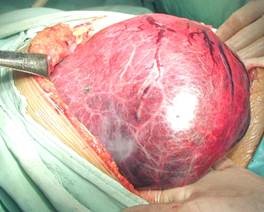

肝母细胞瘤可发生于肝左叶或右叶,以右叶为多。甚至有发生于肝外的迷走肝组织的肝母细胞瘤,近年有腹膜后或腹腔内其他位置的肝脏外肝母细胞瘤的个案报道。肝母细胞瘤大多表现为肝内单个球形或分叶状融合的实性肿块,常使肝叶变形或移位。肿瘤多呈圆形,半数有包膜,但其包膜多非真性的纤维性组织,而是被肿瘤挤压变扁的一层肝组织。肿瘤表面多有粗大的屈曲、显露的血管。早期为单一的瘤体,后逐渐向周围肝组织浸润、扩张,使肝脏呈结节性增大甚至呈巨大的肿块。笔者进行过多例巨大的肝母细胞瘤手术,瘤体的重量占到体重的8分之一,甚至达到体重的5分之一,此为一例6个月患儿,切除瘤肝1,550克, 而手术前患儿带瘤时体重则为7,800克。

肿瘤切面颜色多样,依胆汁和脂肪的含量而定,分化较好的肿瘤呈淡黄绿色,质地均匀,而低分化的肿瘤瘤体呈白色甚至鱼肉状,常有瘤体内的出血及坏死区域。与成人肝癌有明显的差异的一个特点是小儿病例极少合并肝硬化。小儿肝脏左叶比右叶大,肝脏再生能力远比成人旺盛。这一特点尤以新生儿为甚。小儿在肝脏广泛切除手术后,反应较轻。笔者曾经验1例45天日龄4000克体重的肝脏肿瘤患儿,手术切除450克的右三叶瘤肝,约占整个肝脏体积的80%左右。手术后出现黄疸,但两周自然消退,一月后发现残肝明显增生。

2、手术切除 小儿肝母细胞瘤瘤体往往较大,切除的比例常远大于成人。但小儿肝脏再生能力强,有人报告,只要保存20%以上的正常肝组织就能维持生命,而且在2个月内再生后的肝脏可恢复到原来的体积,因此应积极争取肿瘤全部彻底地切除。

手术中根据肿瘤的大小、部位选择术式,可以视情况进行肿瘤切除、肝叶切除、半肝切除或扩大的肝脏多叶切除。对于多例巨大的肝脏肿瘤,笔者先精细解剖第一、第三和第二肝门,预先完全处理相关的门静脉分支、二、三级肝动脉、肝短静脉、肝静脉及胆管,然后阻断第一肝门开始切除肿瘤。近年进行的十余例无一例手术中死亡,均平安度过围手术期。这一手术方法给一些原本无法手术的巨大肝脏肿瘤患者带来新希望。